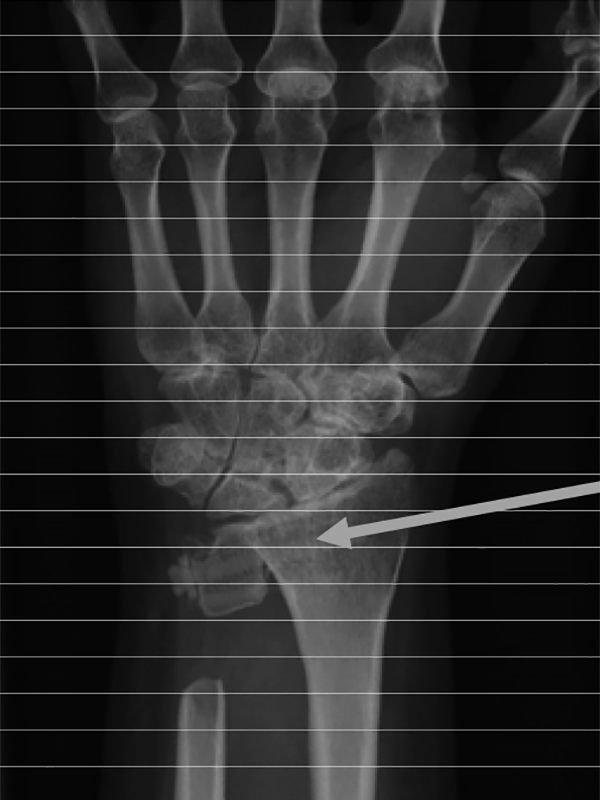

関節リウマチは自己免疫疾患のひとつです。関節滑膜に免疫の異常が起きて滑膜の腫脹、増殖が起こり、痛み、腫れ、こわばりなどの症状が現れます。進行すれば骨や軟骨にびらんと呼ばれる欠損部ができ、さらには関節の変形、破壊に陥ることがあります。図1の赤い部分が関節滑膜の増殖で茶色の部分が骨のびらんです。図2は実際レントゲン写真での骨びらんです。この関節破壊は病気の初期から起こることが分かっていますので早期発見、早期治療が必要です。関節リウマチは、全国に80万人の患者さんがいると推測され女性に多く30~50歳代で多く発病します。

環軸椎亜脱臼

首を前に曲げると頚椎の一部が亜脱臼し、後ろにそらすと戻ります。ここで脊髄が圧迫され手足のしびれや筋力低下、時には脊髄損傷を生じ危険な場合があります。